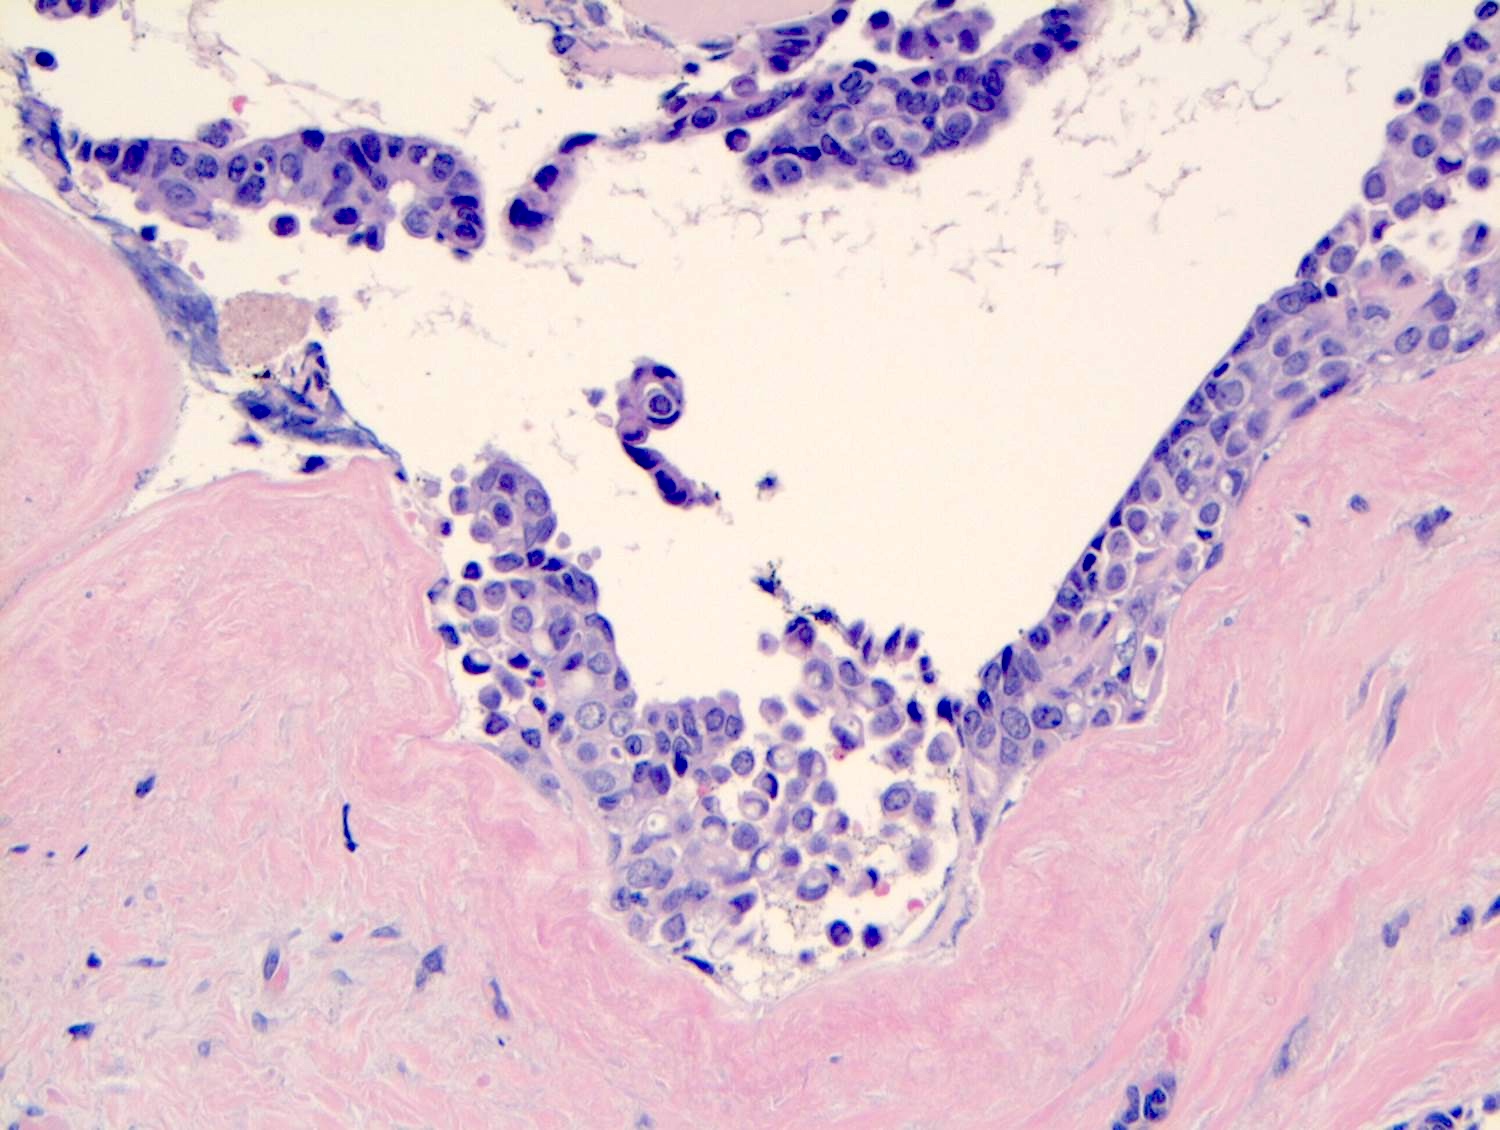

Microscopic (histologic) description

- LCIS involves the terminal duct lobular unit (TDLU), filling and distending acini

- LCIS most often involves lobules but may also grow along the basement membrane of ducts (i.e., pagetoid spread)

- Pagetoid spread in ducts is the characteristic growth of cells between luminal and myoepithelial layers of a duct without destroying ductal epithelium or filling up ductal lumina

- Often makes the ducts appear convoluted; this is called a cloverleaf pattern

- Classic LCIS cells are monomorphic, evenly spaced, loosely cohesive and do not show polarization or gland formation

- Cytoplasm of LCIS cells is typically pale to lightly eosinophilic with indistinct cell borders

- In almost all cases of LCIS, at least some cells contain intracytoplasmic vacuoles or lumina, which may contain an eosinophilic globule; this feature is not specific to LCIS

- Outer layer of myoepithelial cells is retained in the acini and ducts involved but it may be attenuated

Microscopic (histologic) images

Contributed by Anna Biernacka, M.D., Ph.D.